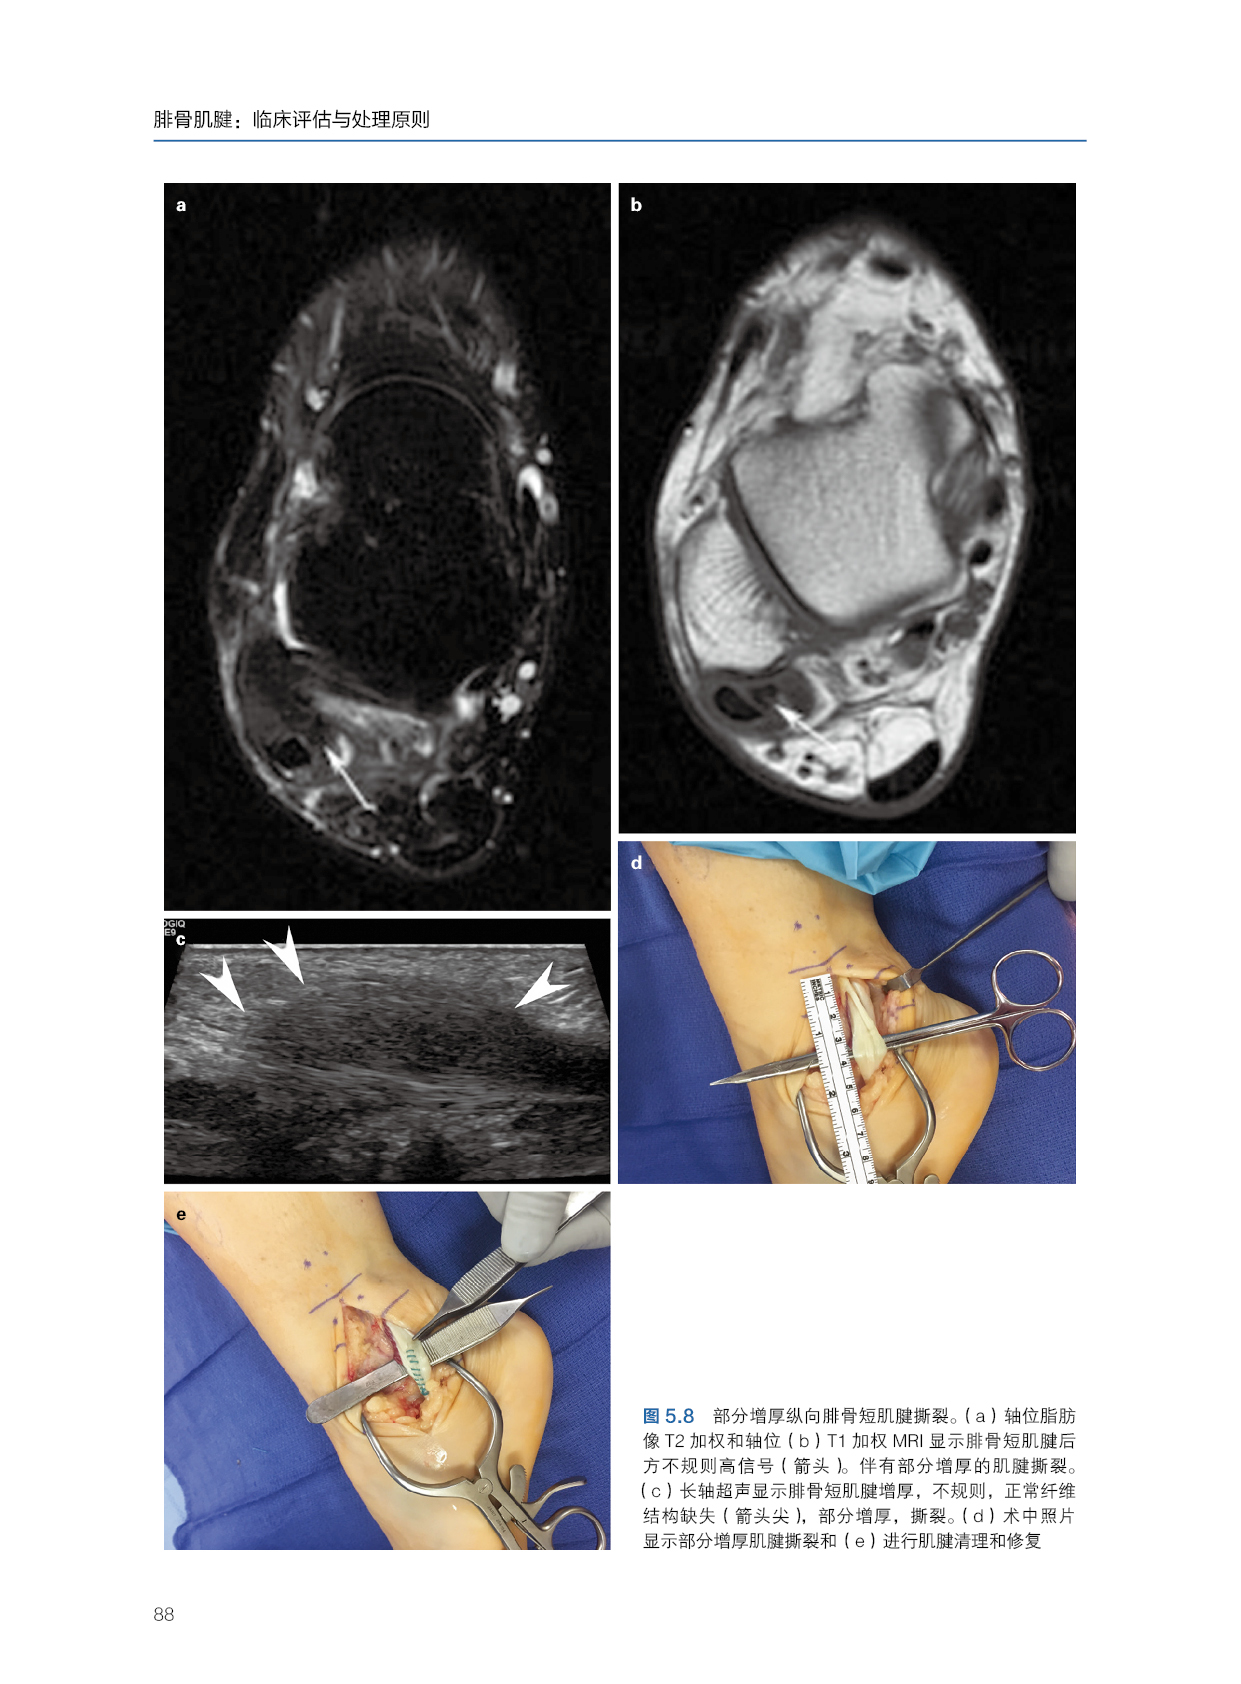

★ 内页插图 ★